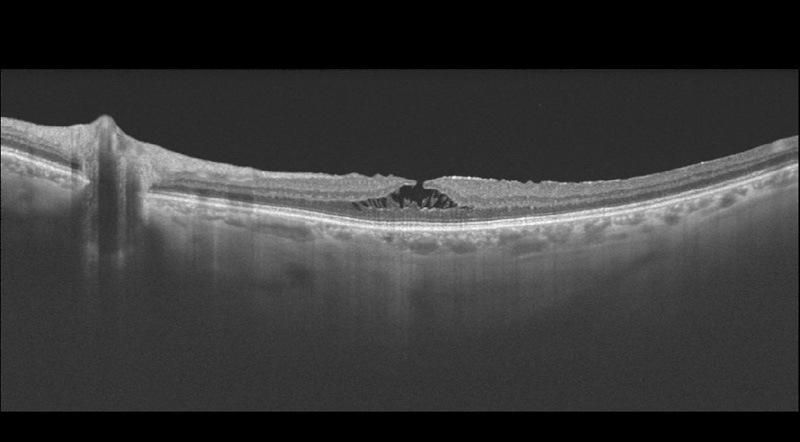

Figura 11. Agujero macular con tracción vítrea.

Figura 16. Agujero macular en estadio IIA.

Figura 17. Agujero macular en estadio IIB, de 208 µm.

Figura 18. Agujero macular en estadio IIB, al mes de realizar cirugía de vitrectomía.

Figura 19. Agujero macular en estadio III.

Figura 20. Agujero macular con tracción vítrea.

Figura 21. Agujero macular mediano o de estadio IIB, de 374 µm.

Figura 22. Agujero macular mediano o de estadio IIB, de 326 µm.

Figura 23. Agujero macular de estadio III, de 459 µm.